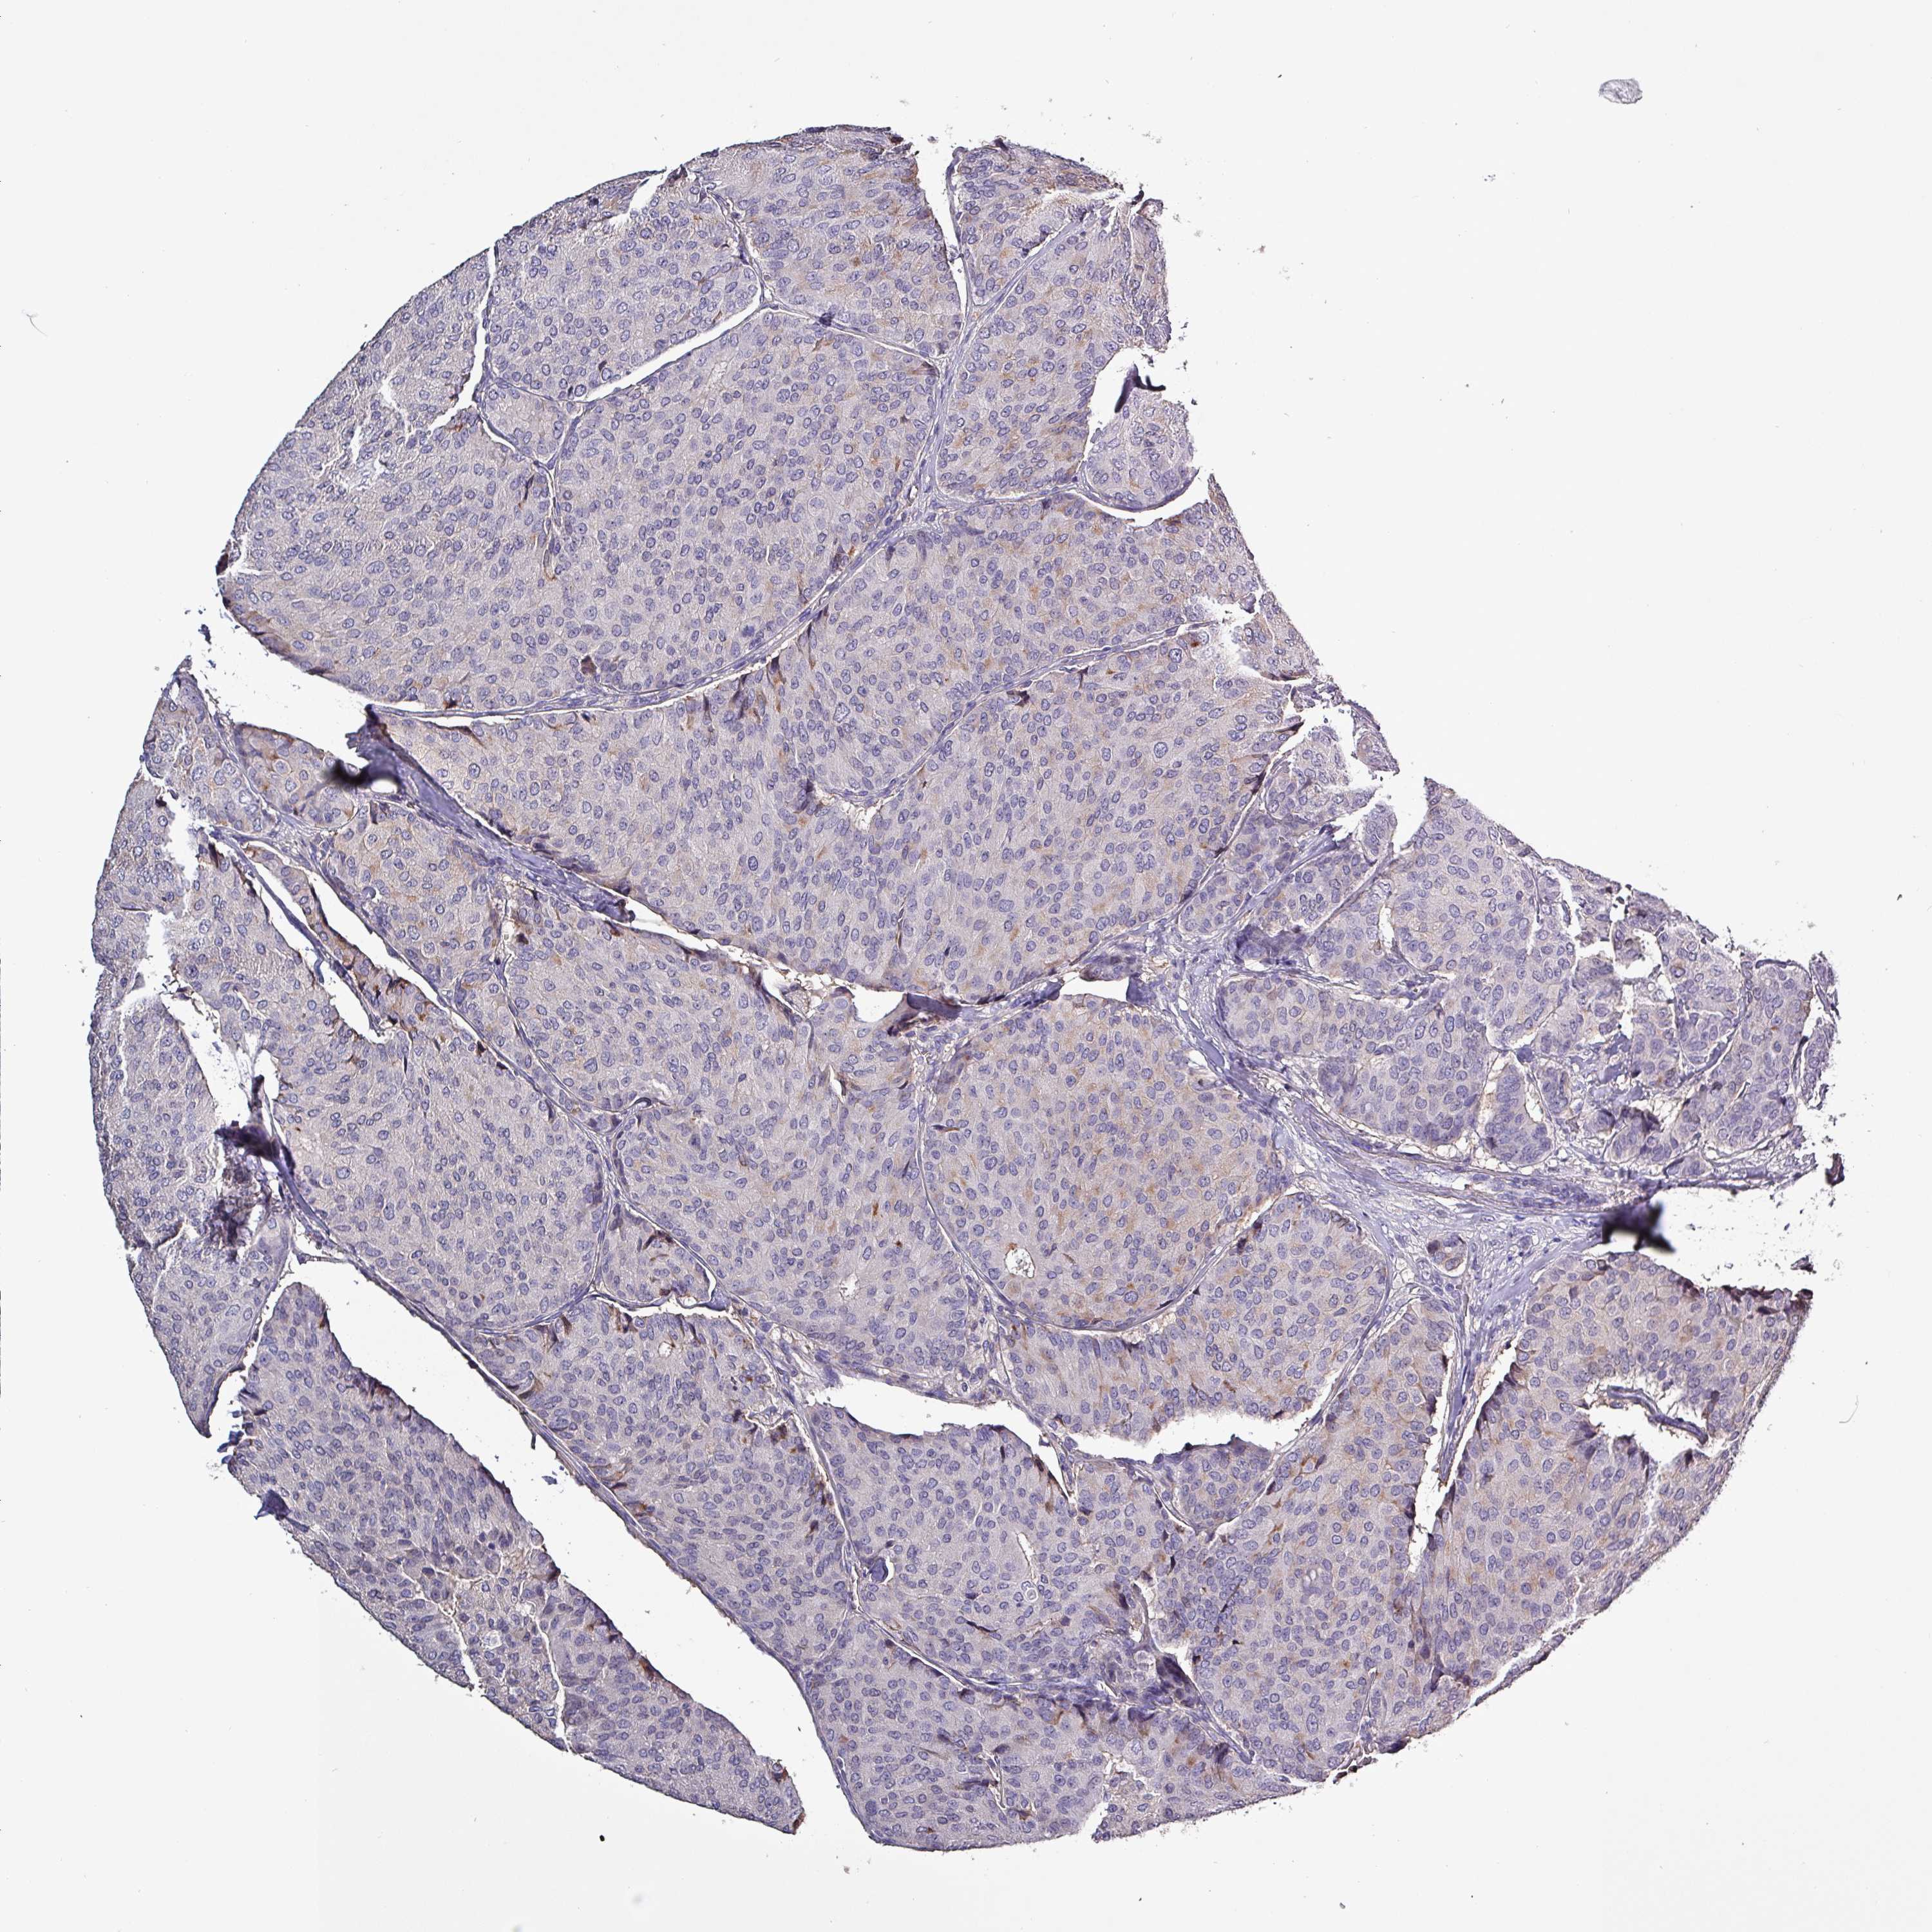

Breast cancer

Human cancer